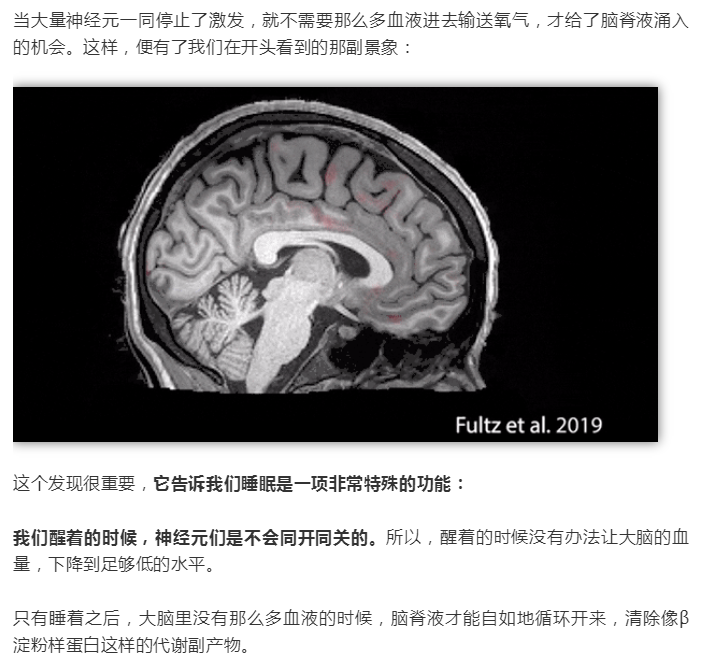

熬夜會變傻?終于有科學(xué)依據(jù)了